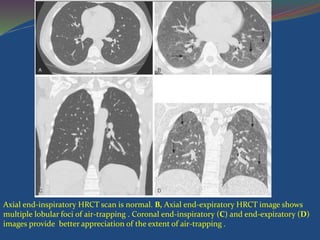

Causes of Constrictive Bronchiolitis

Axial end-inspiratory HRCT scan is normal. B, Axial end-expiratory HRCT image shows

multiple lobular foci of air-trapping . Coronal end-inspiratory (C) and end-expiratory (D)

images provide better appreciation of the extent of air-trapping .